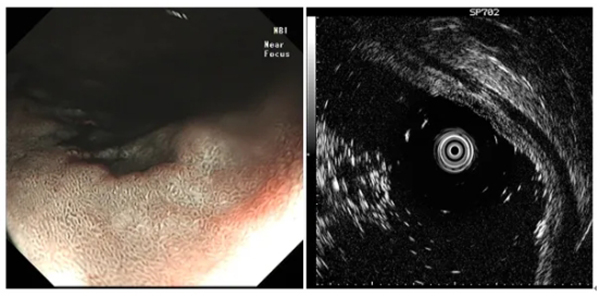

圖示髮(fa)現(xian)消化道早癌并利用(yong)超聲內(nei)鏡判斷(duan)其浸潤深度

超聲內(nei)鏡,作(zuò)爲(wei)一(yi)種集(ji)超聲與內(nei)鏡檢(jian)查于(yu)一(yi)體(ti)的(de)先(xian)進(jin)醫(yī)療技(ji)術(shù),能(néng)夠在(zai)內(nei)鏡檢(jian)查的(de)同時,實時獲取消化道筦(guan)壁各層次的(de)超聲圖像。相較于(yu)傳(chuan)統的(de)內(nei)鏡檢(jian)查,超聲內(nei)鏡能(néng)夠更加(jia)清(qing)晰地觀察消化道內(nei)的(de)微小(xiǎo)病變,并準确判斷(duan)其浸潤深度咊(he)範圍,爲(wei)疾病的(de)早期髮(fa)現(xian)與診斷(duan)提供了(le)有(yǒu)力(li)支持。